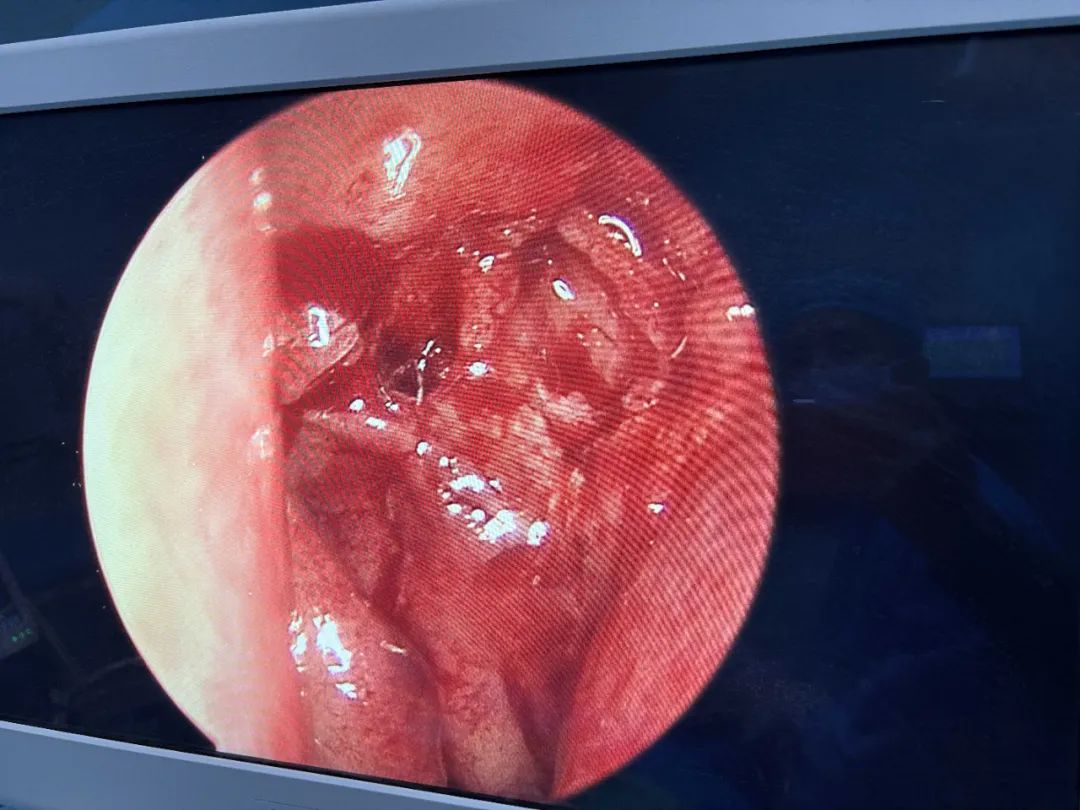

泪囊鼻腔吻合术

泪囊鼻腔吻合术后:泪囊吻合形态良好,术后患者溢泪明显缓解,该手术同时也是河源市首台由眼科医生完成的泪囊鼻腔吻合手术(经鼻镜)。